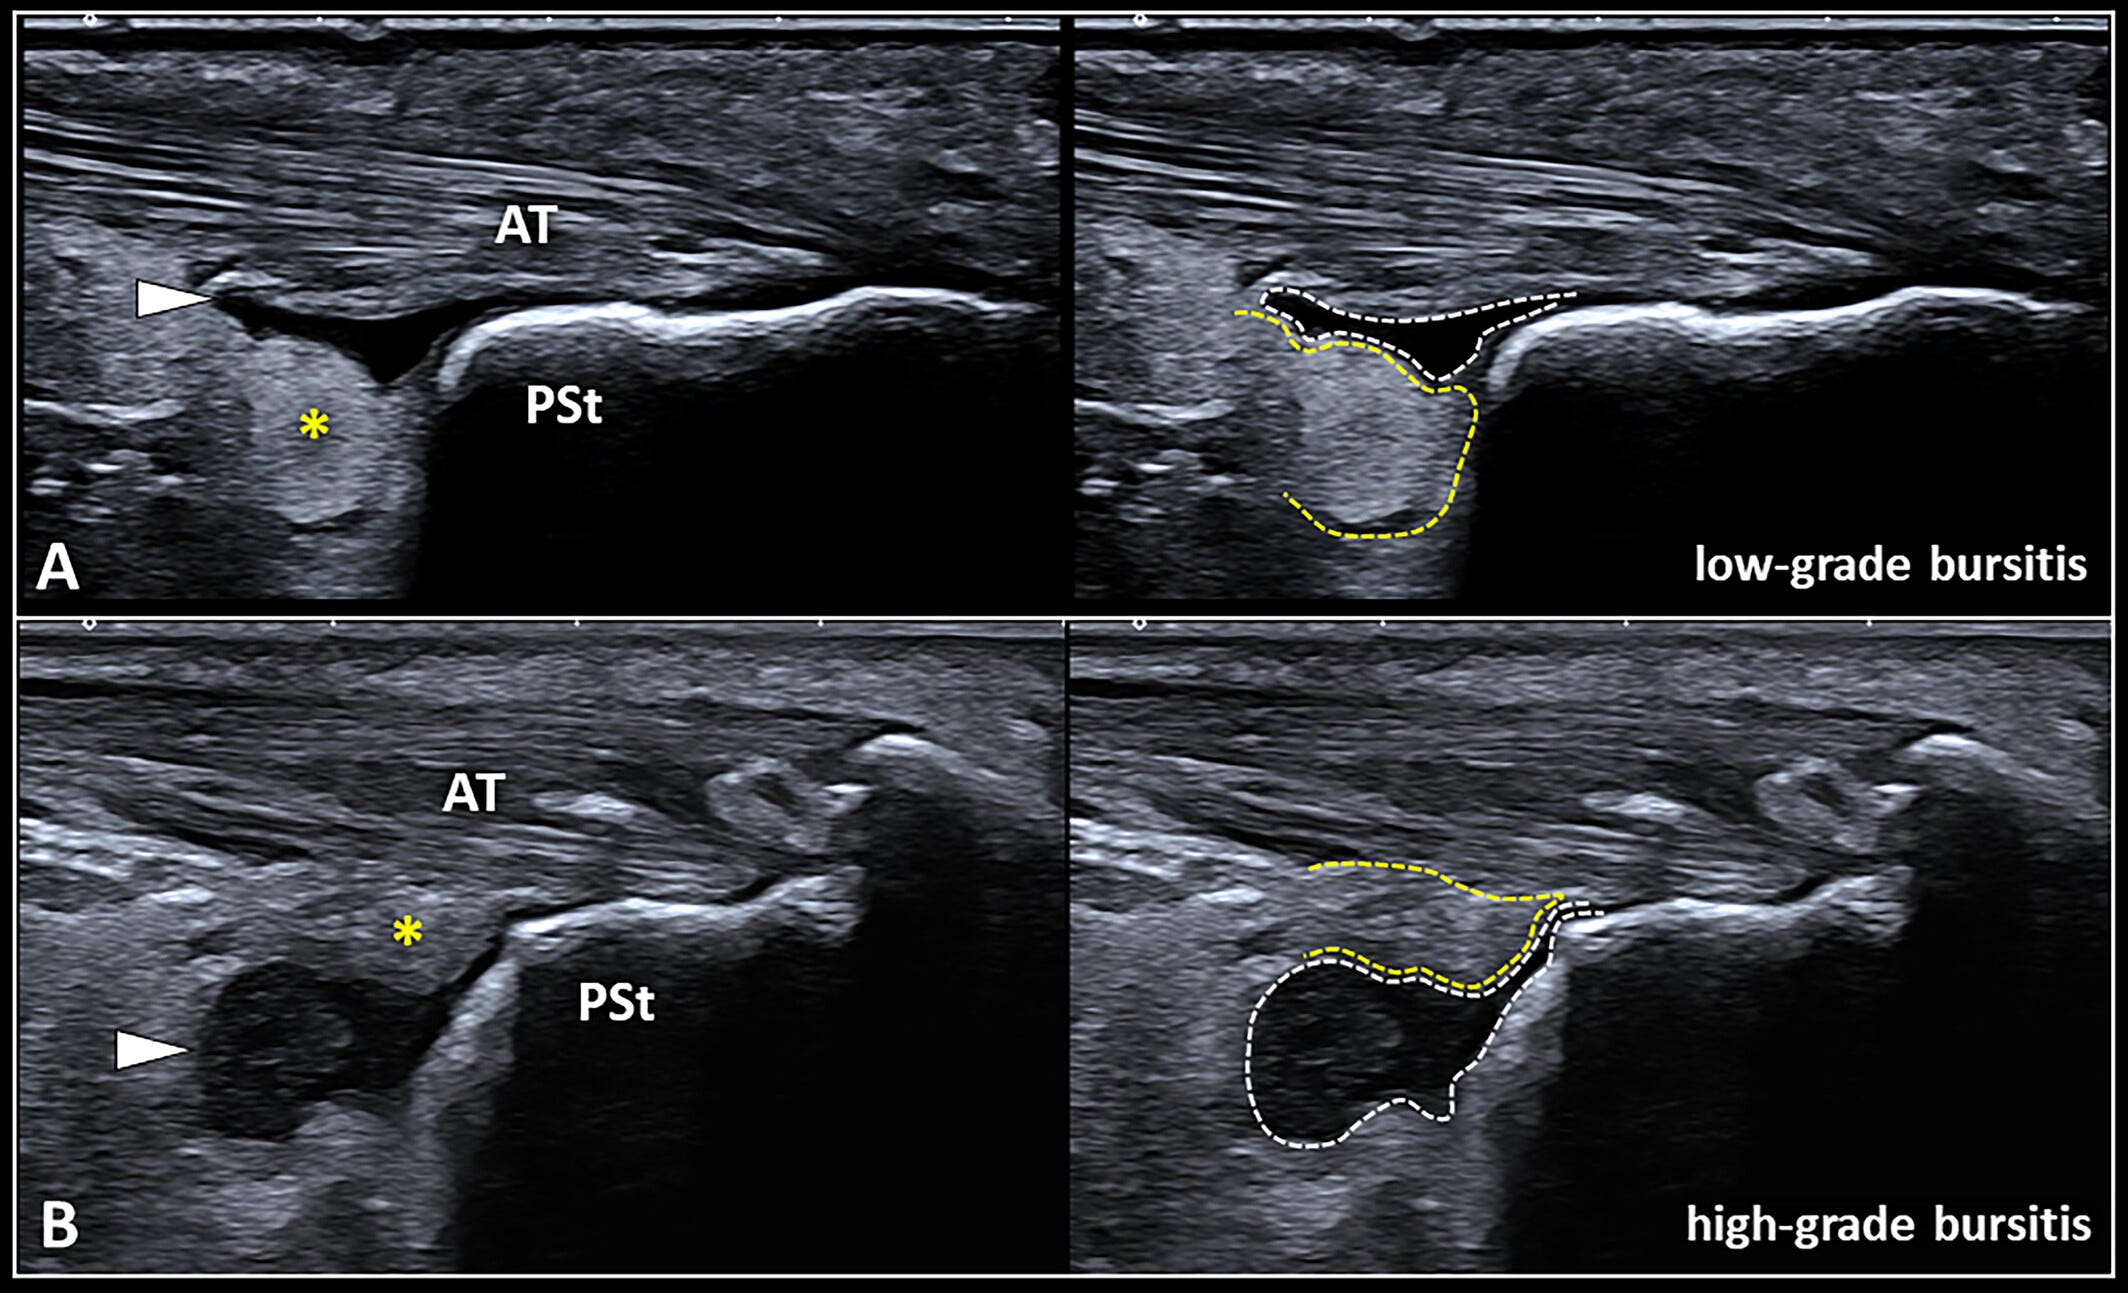

Un derrame bursátil (punta de flecha blanca) que ocupa un espacio inferior al tejido graso (asterisco amarillo) dentro de la región retrocalcánea representa una bursitis de bajo grado (A).

Por el contrario, un derrame bursátil (punta de flecha blanca) que ocupa un espacio igual o superior al de la almohadilla grasa de Kager (asterisco amarillo) representa una bursitis de alto grado (B).

AT: tendón de Aquiles;

PSt: tuberosidad posterosuperior del calcáneo;

línea discontinua blanca: espacio ocupado por el derrame bursátil;

línea discontinua amarilla: espacio ocupado por el tejido graso retrocalcáneo.